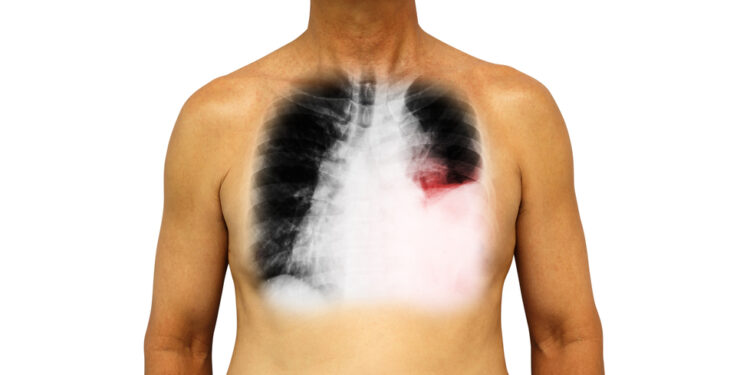

- Vaizdiniai tyrimai: rentgeno nuotraukos, kompiuterinė tomografija, ultragarsas. Jie padeda nustatyti, ar pleuros ertmėje yra susikaupusio skysčio ar pūlių.